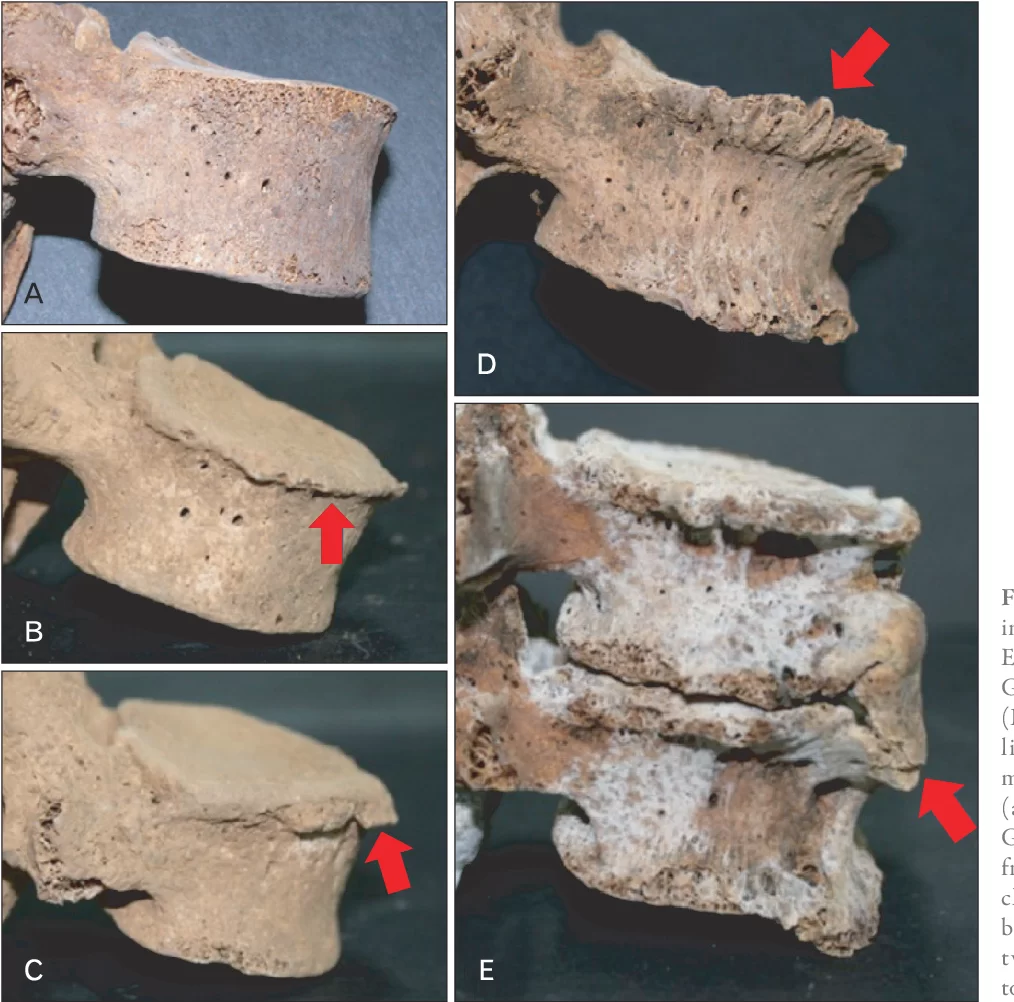

Τα οστεόφυτα γενικά είναι μικρές προβολές και εκβλαστήσεις των οστών και συγκεκριμένα των σπονδύλων. Με απλά λόγια, όταν μιλάμε για οστεόφυτα μιλάμε για νέο οστό το οποίο δημιουργείται με τον καιρό, στις άκρες των σπονδύλων (Εικόνα 1). Τα οστεόφυτα αναπτύσσονται κοντά σε αρθρώσεις, δηλαδή εκεί που συναντώνται δύο οστά και μπορούν να εμφανιστούν σε ολόκληρο το μήκος της σπονδυλικής στήλης. Δηλαδή στην αυχενική, θωρακική και οσφυϊκή μοίρα.